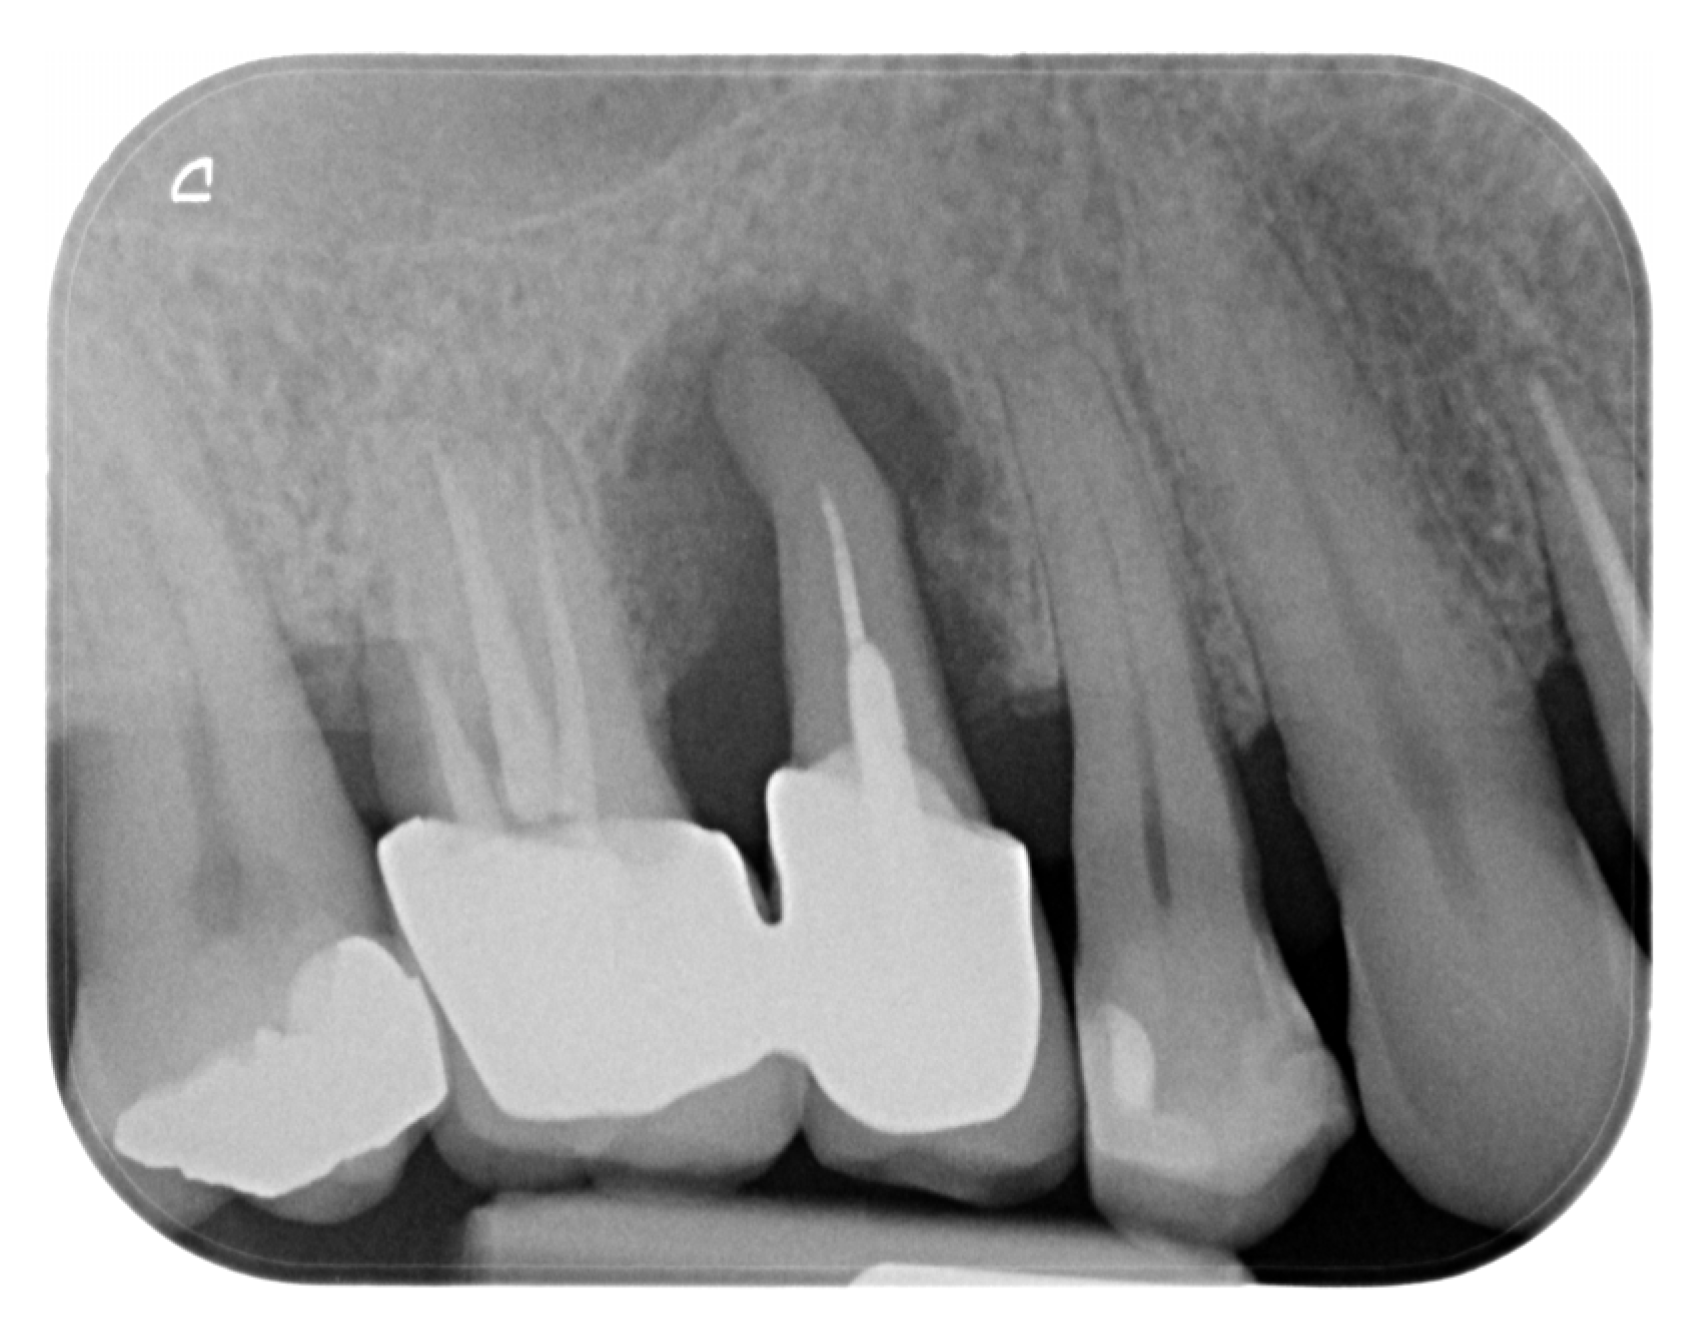

A 45-year-old male patient, non-smoker, non-diabetic, and without systemic comorbidities, was referred for periodontal treatment. Perioperative radiographic assessment identified a diffuse peri-radicular radiolucency at the maxillary right second premolar, consistent with an endo-periodontal lesion and confirming the need for extraction (Figure 1).

Figure 1.

Initial X-ray status prior to clinical examination.